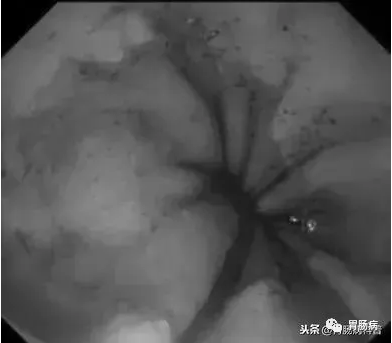

我們再次返回食道內(nèi),發(fā)現(xiàn)持續(xù)有少量鮮血附著于管壁上,邊退鏡邊沖洗,在食道入口處發(fā)現(xiàn)血液量增多,但因食管上括約肌及環(huán)咽肌收縮,入口處黏膜觀察不清,后在胃鏡前端使用透明帽后,視野改善很多。

如下圖:

在食道入口,距門齒約18至20cm處可見片狀黏膜剝脫及條索狀裂傷,持續(xù)滲血。

此時終于查明消化道出血原因,為患者的下一步治療指明方向。